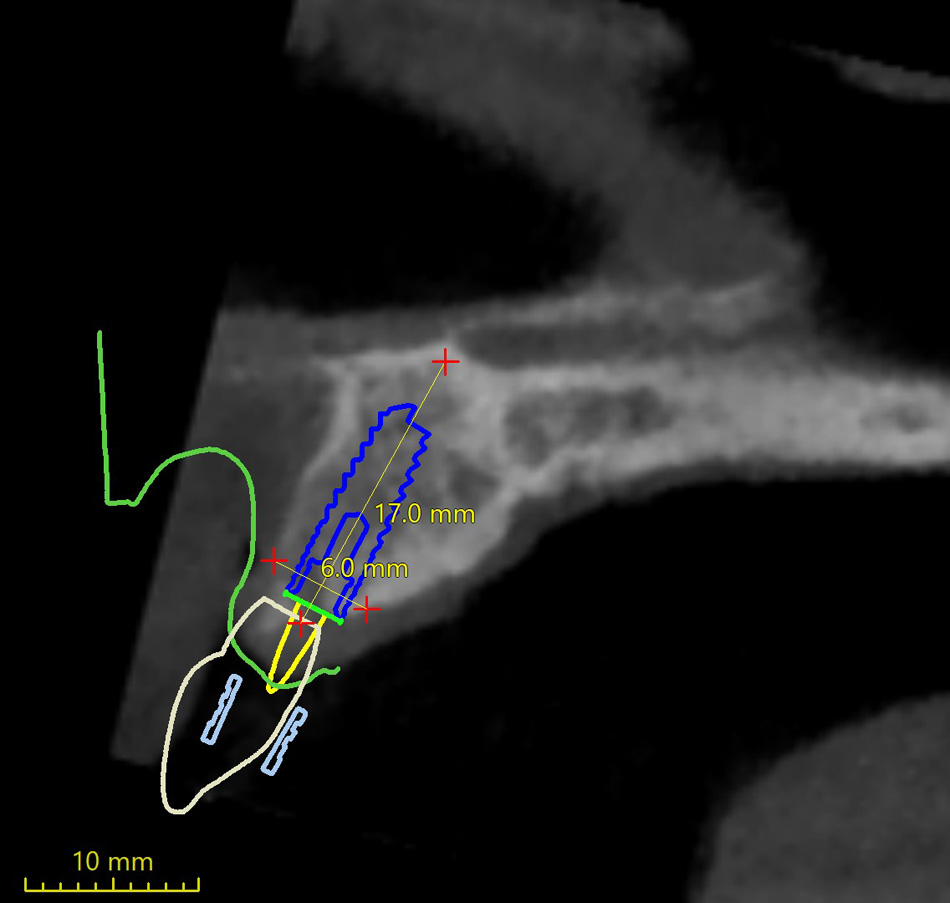

Jedná se o externí plánovací program, spojený se zubní laboratoří a frézovacím centrem, který využívá dat získaných z 3D rentgenu čelisti, otisku zubů a dásně (scanu zubů a dásně) a finálního návrhu protetické náhrady. Tento program umožňuje tříprostorovou počítačovou simulaci při plánování pozic implantátů. Součástí programu je i databáze, ve které mohou být uloženy všechny typy implantátů od všech výrobců, včetně jejich délek, průměrů i tvarů.

Lékař si vytvoří všechny typy zobrazení potřebných pro naplánování – tedy 2D snímky (panoramatický), příčné řezy i 3D model.

Vidí zde i důležité anatomické útvary – čelistní dutinu, průběh nervu atd. Po proměření množství kosti – šířky i výšky vybere z databáze vhodný typ implantátu a umístí ho do požadované lokality. Ihned vidí jeho pozici ve všech 3 rovinách a na všech snímcích i 3D modelu. Může upravovat podle potřeby jeho pozici, sklon atd.

Všechny vybrané a správně umístěné simulované implantáty se ukládají do „počítačové karty“ pacienta s jejich pozicí, délkou, průměrem, typem i sklonem. V programu také lékař navrhuje chirurgické šablony pro řízenou nebo navigovanou implantaci. Lékař i pacient tedy ještě před vlastní operací vidí, jak by mělo ošetření probíhat a vypadat.